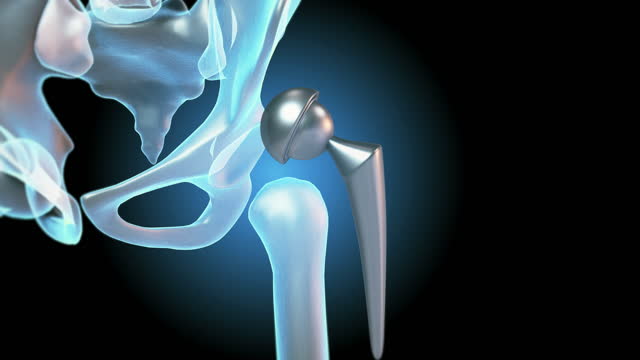

고관절 통증 증상 치료와 관리

고관절 통증을 관리하고 치료하기 위해서는 다양한 요인을 고려해야 합니다. 통증을 완화하고 원인을 해결하기 위해 개별 환자에게 맞춤형 치료 계획이 필요합니다. 이때, 관절과 근육의 조화로운 기능을 회복시키기 위한 재활운동이 중요합니다.